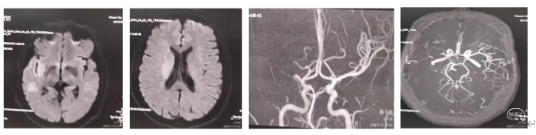

病情简介:

患者Lgh,女性,57岁,"突发左侧肢体失动,言语不清,恶心呕吐3小时"(7月2日)入院。查体:左侧下肢肌力I级,上肢肌力0级,言语含糊不清,双眼向右侧凝视。NiHSS评分8分。体重58Kg,心电图示:房性早搏。既往史:无高血压、糖尿病史。MRl:Dwl显示右侧大脑中动脉区和内囊略高密度改变,皮层多处小点状高密度改变。ASPECT评分6分。MRA显示:右侧大脑中动脉M1起始部以远未显影,考虑闭塞。

诊断:急性右侧大脑中动脉闭塞性脑梗塞。

1.行TNK16mg静脉溶栓,继之给予甲泼尼龙120mg(2mg/Kg)。溶栓后患者左下肢肌力1级,左上肢O级,言语含糊好转,查体合作。

2.脑血管造影示:右侧大脑中动脉M1以远末显示,副大脑中动脉有少量供血。M1段似有血栓影

3.取栓8F指引导管置于C1段,中天远端通路导管裸奔至M1段,导管尾部连接延长管,5OmL注射器"踹马桶"抽吸,无回血,负压下撤出体外,检查结果见约0.5cm大小白色血栓和少量点片状红色血栓。

4、快速二次接续抽吸:清理可能的残余血栓后造影右侧大脑中动脉血流通畅,未见明确血栓逃逸和狭窄。结束手术。

术后情况:意识清楚,言语流利,左侧下肢肌力3级,上肢肌力1级。